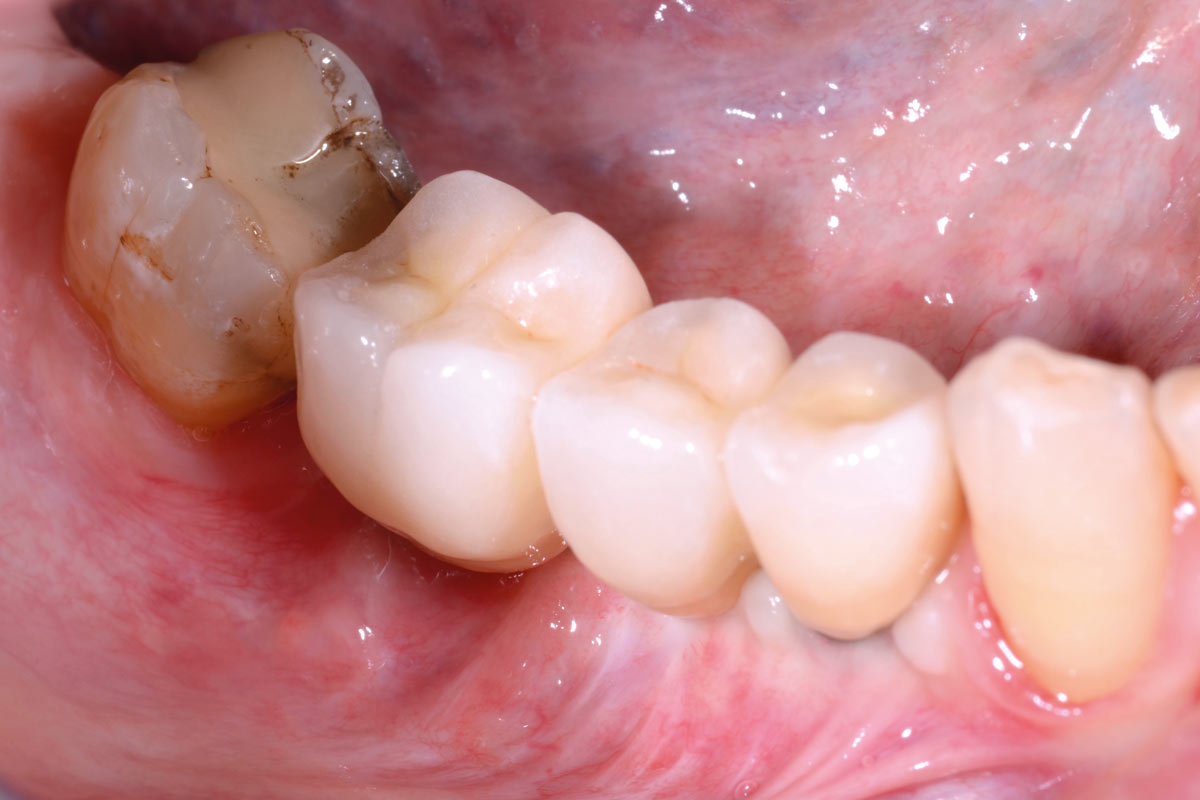

01/29 - Initial clinical situation with pronounced vertical and horizontal bone defectVertical bone augmentation and broadening of attached gingiva using cerabone®, permamem® and mucoderm® - Dr. R. Naimoli

Initial clinical situation with pronounced vertical and horizontal bone defect